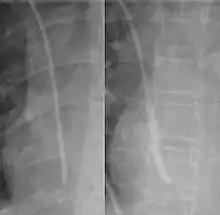

During subclavian vein central line placement, the catheter can be accidentally pushed into the internal jugular vein on the same side instead of the superior vena cava. A chest x-ray is performed after insertion to rule out this possibility.[25] The tip of the catheter can also be misdirected into the contralateral (opposite side) subclavian vein in the neck, rather than into the superior vena cava.

The line is then inserted using the Seldinger technique: a blunt guidewire is passed through the needle, then the needle is removed. A dilating device may be passed over the guidewire to expand the tract. Finally, the central line itself is then passed over the guidewire, which is then removed. All the lumens of the line are aspirated (to ensure that they are all positioned inside the vein) and flushed with either saline or heparin.[1] A chest X-ray may be performed afterwards to confirm that the line is positioned inside the superior vena cava and no pneumothorax was caused inadvertently. On anteroposterior X-rays, a catheter tip between 55 and 29 mm below the level of the carina is regarded as acceptable placement.[36] Electromagnetic tracking can be used to verify tip placement and provide guidance during insertion, obviating the need for the X-ray afterwards.

Chest x-ray with catheter in the right subclavian vein

The outline of superior vena cava on a chest X-ray is labeled at left.